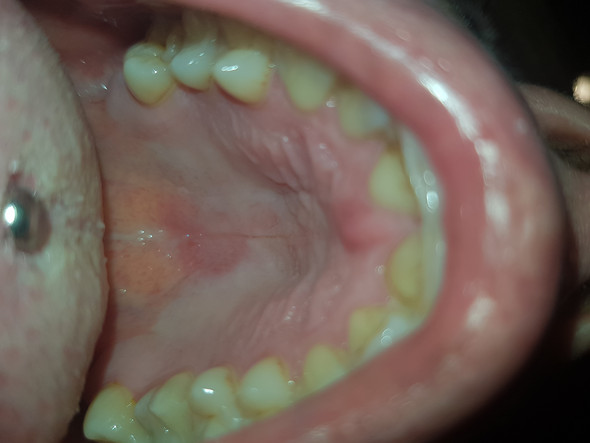

Offene stelle am gaumen. Sie haben ein zu hartes Brötchen mit Kanten und schon ist es passiert die Haut und weiteres Gewebe werden im Mundraum verletzt. Die Heizungsluft trocknet die Lippen aus mit der Zahnseide hat man sich das Zahnfleisch verletzt oder es kribbelt schon wieder ein Herpesbläschen eine kleine Wunde im Mund entsteht schnell. Einer Woche eine offene Stelle am Gaumen direkt hinter den Zähnen.

Wunden im Mund oder offene Stellen im Mund sind belastend und behindern beim Kauen und Essen. Doch es gibt einfache Mittel die eine Wunde im Mund sanft lindern. Offene stelle am gaumen was tun.

Diese wird genau untersucht. Eine Entzündung am Gaumen fällt meist durch eine schmerzhafte Schwelllung und Rötung auf. Beschwerden am gaumen bei zahnschmerzen hintergrund können zahnschmerzen sein die sich auf den gesamten mund rachen bereich ausdehnen und damit auch den gaumen betreffen können einleitung eine entzündung am gaumen fällt meist durch eine schmerzhafte schwelllung und rötung auf.

Vorgestern Abend habe ich mich beim essen in Asien verbrannt seit dem hatte ich wenn ich mit der Zunge den Gaumen berühre ein brennendes Gefühl.

Recurrent aphthous stomatitis oral apthous ulcers sind kleine weiße oder rote offene Stellen oder Geschwüre der Mundschleimhaut der Zunge oder des Gaumens. Die sorgt dafür dass aus dem Zucker im Honig Wasserstoffperoxid. Entzündung am Gaumen - Dr-Gumpert. Diese kann aufgrund von Verletzungen Infektionen allergischen Reaktionen oder gar Verbrennungen auftreten. Eine Entzündung am Gaumen fällt meist durch eine schmerzhafte Schwelllung und Rötung auf. Beschwerden am Gaumen bei Zahnschmerzen Hintergrund können Zahnschmerzen sein die sich auf den gesamten Mund-Rachen-Bereich ausdehnen und damit auch den Gaumen betreffen können Einleitung Eine Entzündung am Gaumen fällt meist durch eine schmerzhafte Schwelllung und Rötung aufDiese kann aufgrund von Verletzungen Infektionen allergischen. Ich hoffe ich bin im richtigen Forum. Der Begriff kommt aus dem Griechischen und bedeutet Schwämmchen. Beim Kauen oder bei Kontakt mit Fruchtsäure.

Hallo ich habe seit ca. Offene stelle am gaumen was tun Gaumenschmerzen. Eine Entzündung am Gaumen fällt meist durch eine schmerzhafte Schwelllung und Rötung auf. Zu diesem Zweck eignen sich Kräuter wie Johanniskraut Kamille Lindenblüten und Nelken die zu einem Tee zubereitet werden. Beim Kauen oder bei Kontakt mit Fruchtsäure. Eine leichte Gaumenreizung kann man schon von zu heißen Nahrungsmitteln bekommen. Aphthen sind eine der häufigsten Krankheiten der Mundschleimhaut.